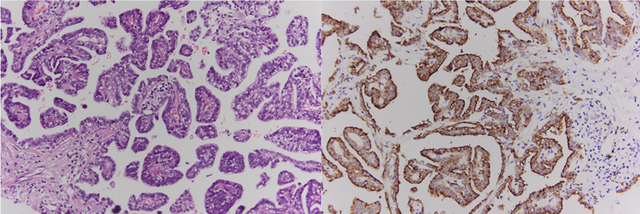

Kết quả mô bệnh học và hóa mô miễn dịch cho thấy đây là ung thư biểu mô tuyến nhú của phổi. Ảnh: BVCC

Kết quả mô bệnh học và hóa mô miễn dịch xác định đây là ung thư biểu mô tuyến nhú của phổi. Các tế bào u dương tính với TTF-1, Napsin A và CK7.

Đây là một phân nhóm hiếm của ung thư phổi không tế bào nhỏ, đặc trưng bởi cấu trúc nhú, khả năng xâm lấn và di căn cao. Tiên lượng bệnh phụ thuộc lớn vào việc phát hiện sớm và điều trị kịp thời.